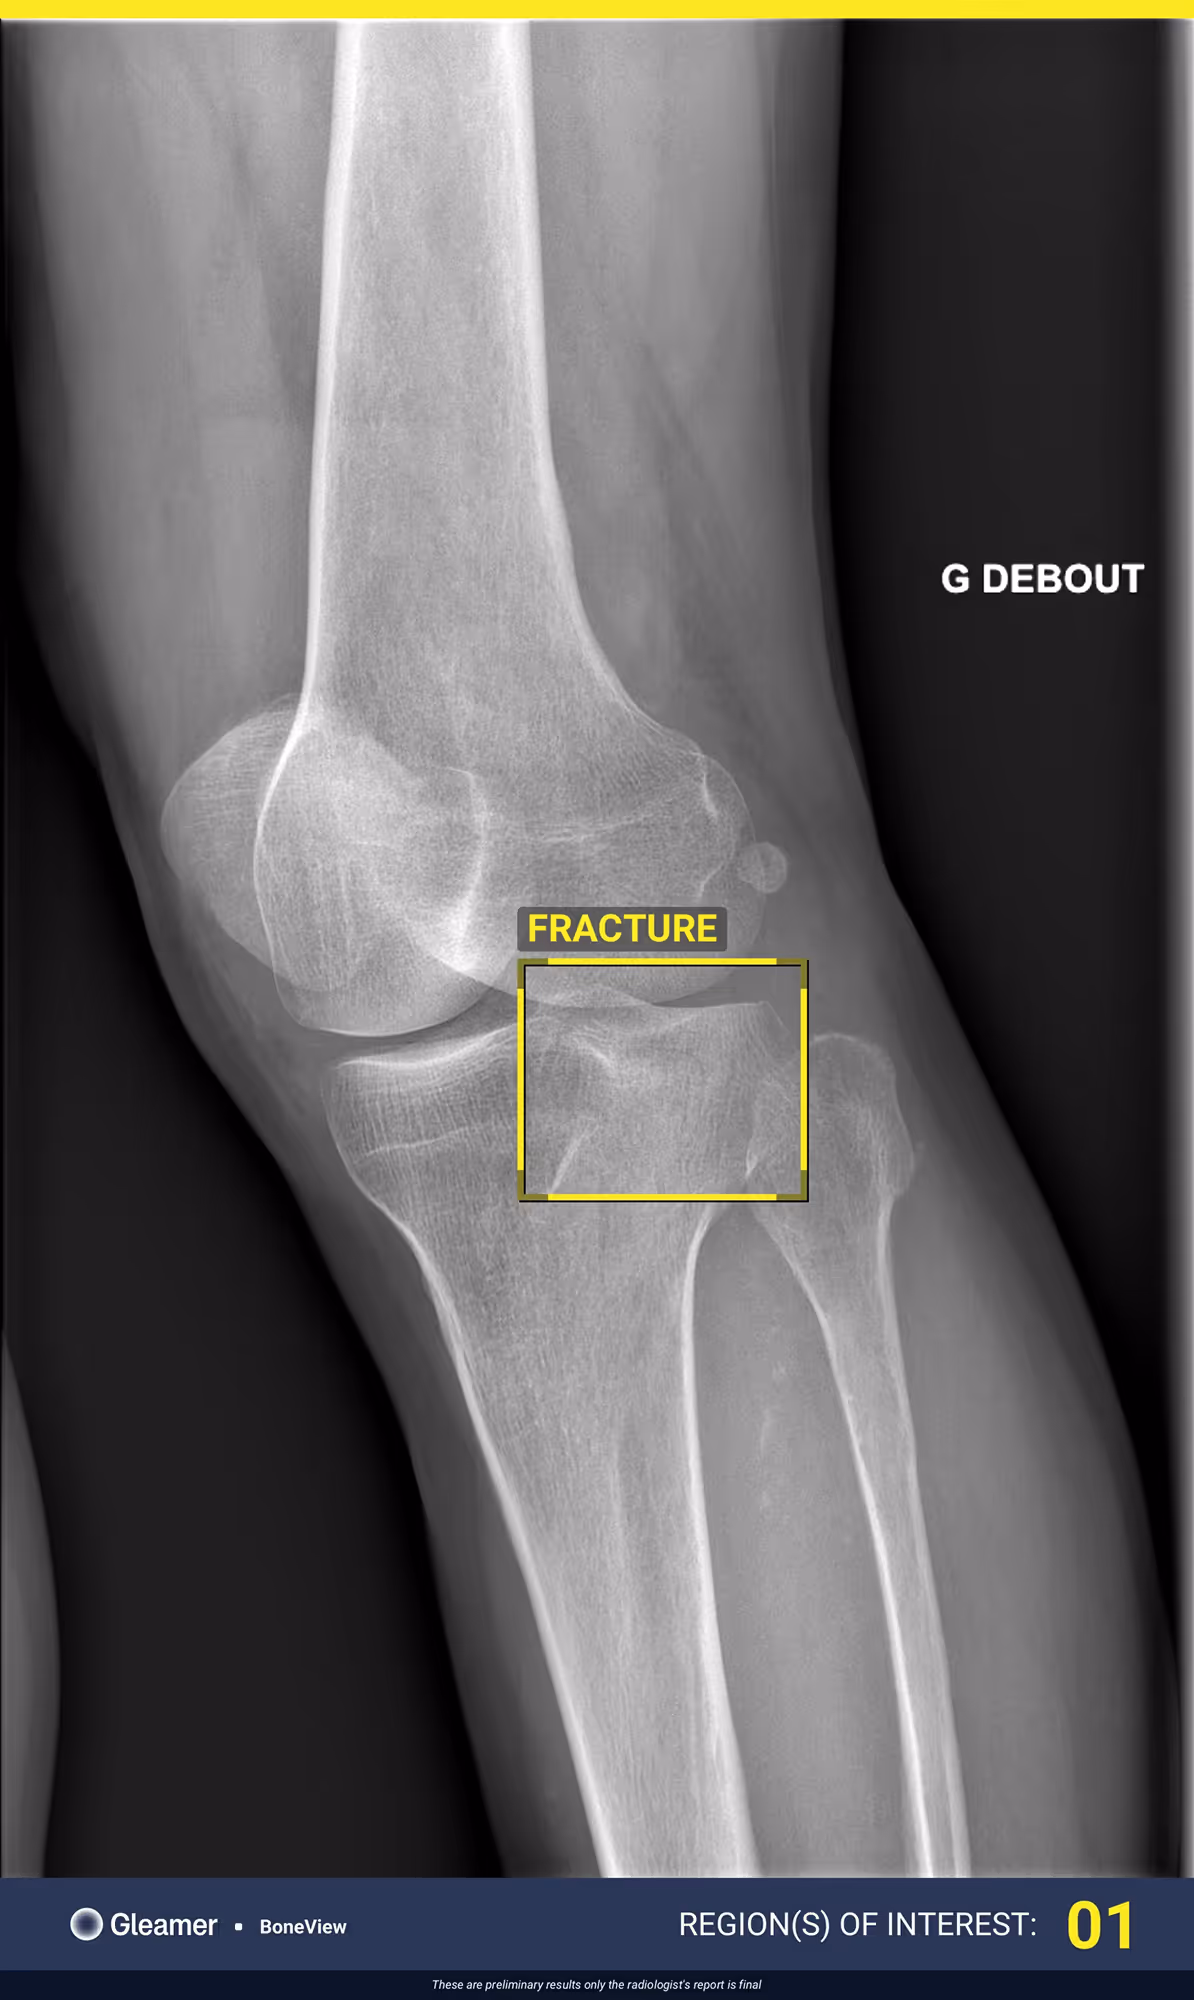

A 63-year-old male with lingering pain after a trail run.

Results

BoneView detected a fracture of the lateral tibial plateau and associated effusion. The fracture has a high risk of displacement.